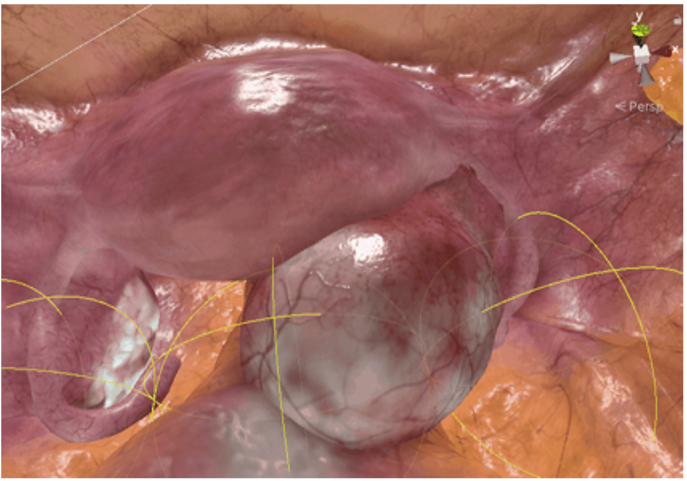

Patient-Specific Rehearsal

Patient-derived training scenarios (R&D / training use). Patient-specific rehearsal is in development and subject to regulatory review.